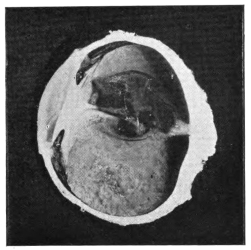

PLATE IV.

22.

LENS DISLOCATED BEHIND RETINA

curly bracket span

23.

FISTULA OF THE CORNEA

24.

CAPSULO-CORNEAL SYNECHIA

25.

RETINO-CORNEAL SYNECHIA

26.

SCLERAL FISTULA

27.

"    " (MAGNIFIED)